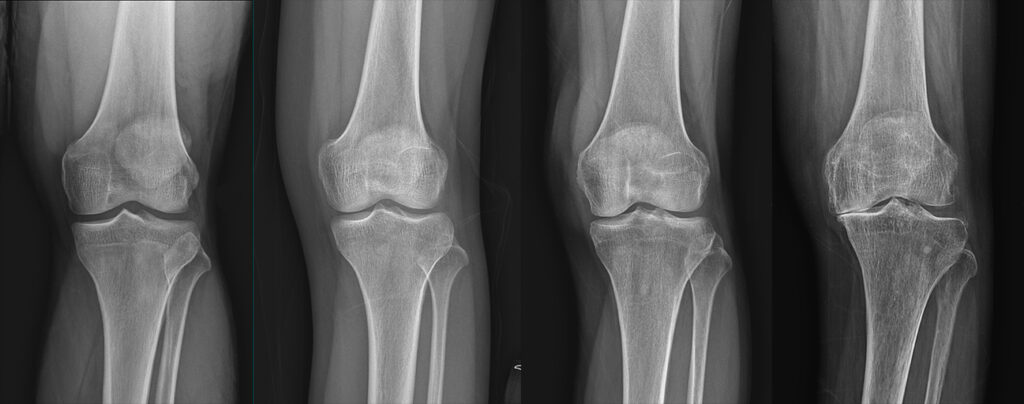

진단은 통증 부위를 중심으로 이학적 검사와 영상 검사를 병행합니다. 기본적으로 골반 및 엉덩이, 허리의 X-ray를 통해 구조적 이상을 확인하고, 필요 시 초음파, CT 또는 MRI로 보다 정밀한 평가를 합니다.